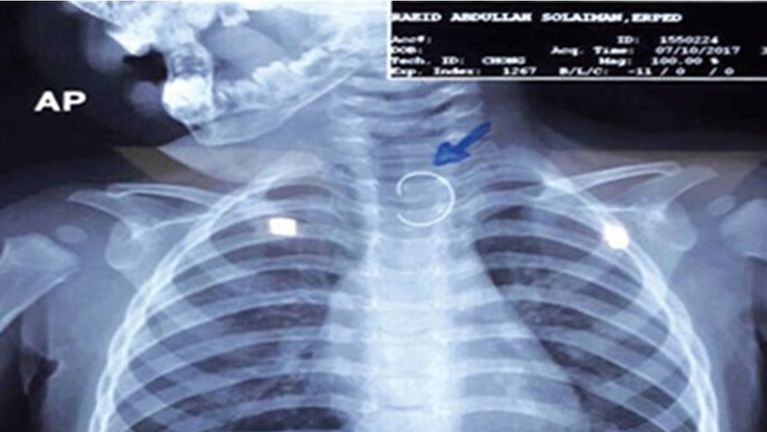

وأوضح الدكتور محمد متولي في مداخلة هاتفية لبرنامج "خط أحمر" الذي يقدمه الإعلامي محمد موسى على قناة الحدث اليوم، أن الأطفال في هذه السن غالبًا ما يبتلعون أي جسم يقع أمامهم، سواء كان طعامًا أو أشياء معدنية صغيرة، مضيفًا أن الطفلة بلعت دبوس المكتب الذي يثبت الأوراق، وظل عالقًا في جدار المريء، ما استدعى إجراء أشعة للتأكد من وجود الجسم الغريب قبل تجهيزها للعملية.

وأشار إلى أن خطورة الحالة كانت كبيرة، إذ كان الدبوس محاطًا بأنسجة المريء، وقد يؤدي أي خطأ إلى ثقب المريء، التهاب الصدر، أو الوفاة، وقال: "كنا نضع أيدينا على قلوبنا أثناء العملية حتى نخرج الدبوس بأمان".